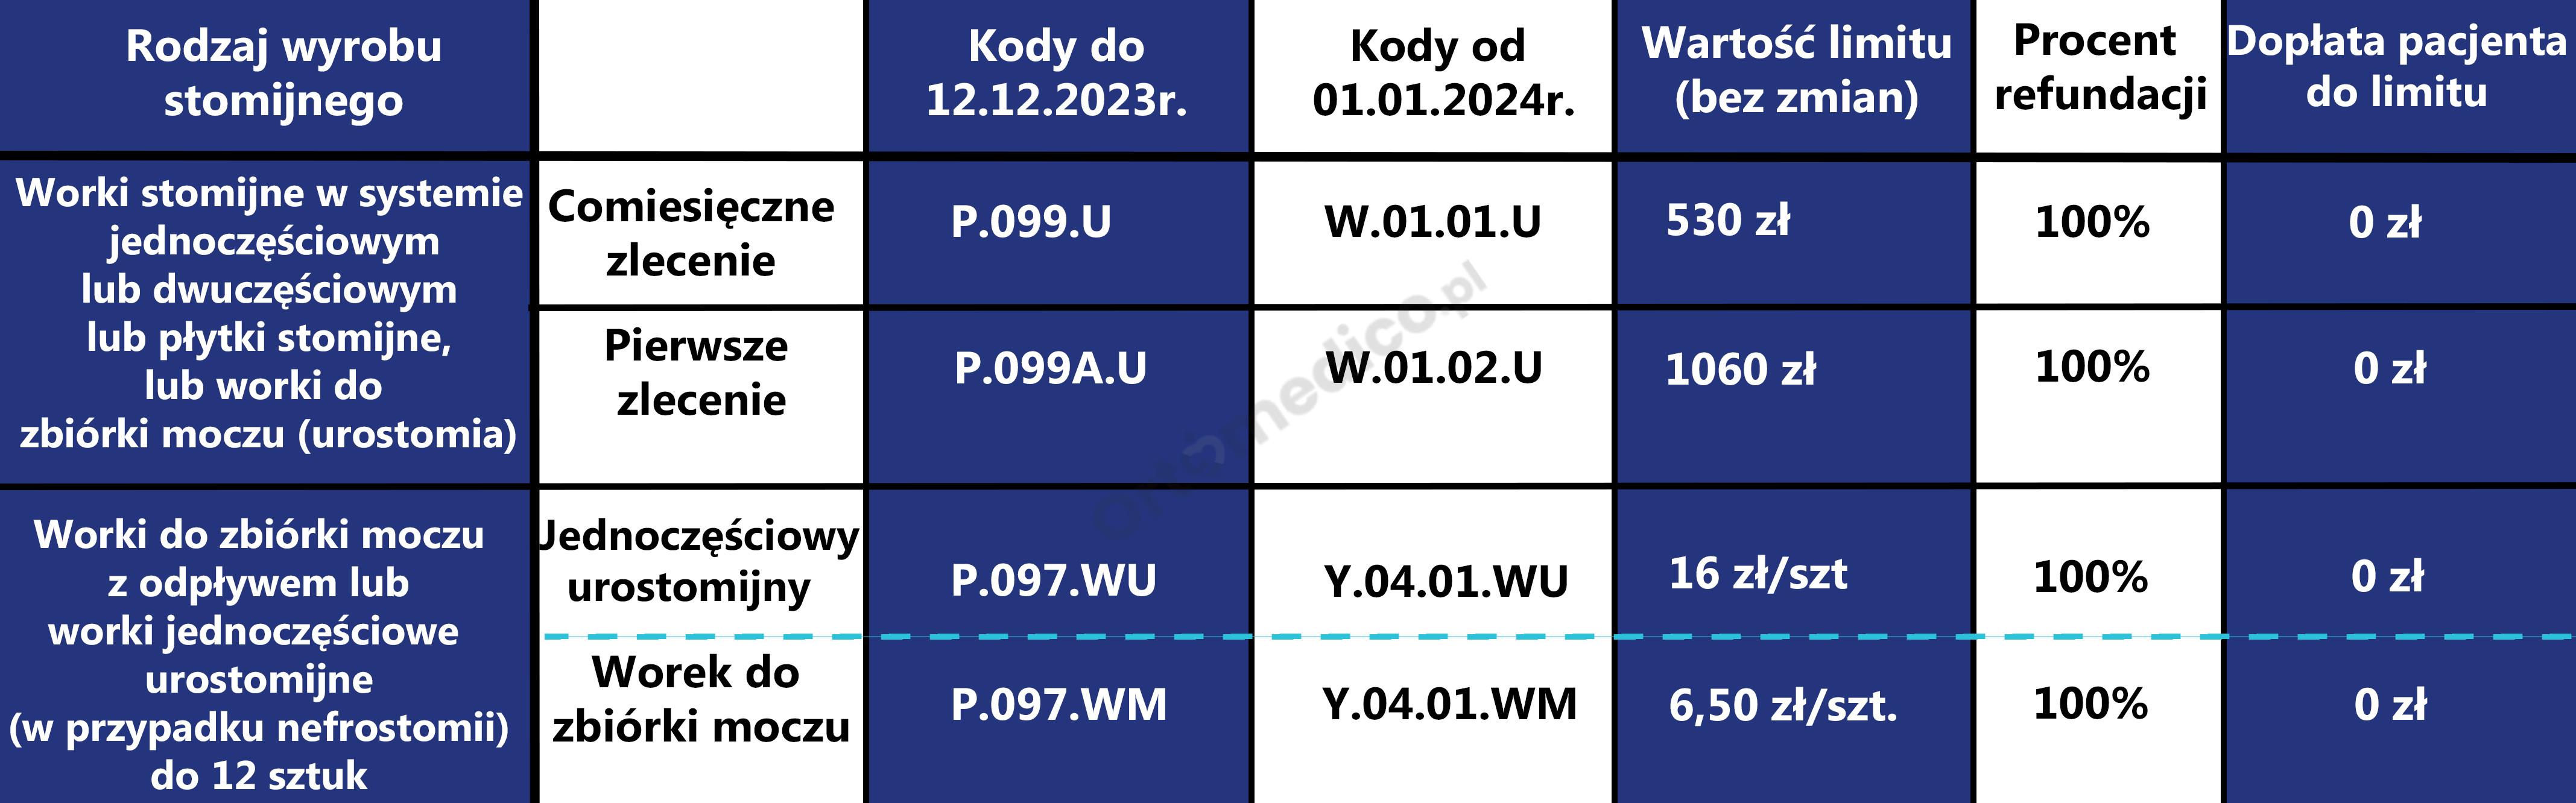

- Uniwersalny łącznik w kształcie stożka: Stożkowy łącznik umożliwia łatwe i szybkie podłączenie worka do różnych typów cewników wewnętrznych (urologicznych), zewnętrznych oraz worków urostomijnych. Zapewnia to wszechstronność i uniwersalność użytkowania.

- Uniwersalny łącznik w kształcie stożka: Stożkowy kształt łącznika umożliwia łatwe i bezpieczne podłączenie worka do różnych typów cewników (wewnętrznych, zewnętrznych) oraz worków urostomijnych. Jest on zaprojektowany tak, aby zapewnić pewne i szczelne połączenie.